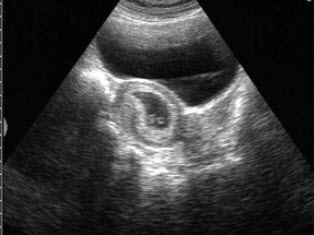

8、单项选择题

男性,于晨前起床时阴囊急剧疼痛,超声见睾丸肿大,CDFI:血流信号消失。如图所示,考虑为()

A.附睾炎

B.睾丸炎

C.睾丸扭转

D.睾丸肿瘤

E.睾丸结核